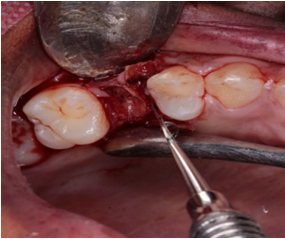

For extraction of the started unit, anesthesia with Lidocaine HCL 2% + epinephrine 1: 100,000 were performed. Thus, infraorbital nerve block and papillary complementation were performed. Then, an intrasucular incision (selected 15C) was made, followed by detachment of the gingival tissue with the Molt No. 9 detacher (Figure 2). Immediately after detachment, initiate the procedure of periodontal ligament dislocation (LP) and disconnection of the root remnant, due to the need for minimal trauma for the conservation of the alveolar walls, try an atraumatic extraction of the units using the straight chelate period ®(Figure 3). Next, the alveolus was curettable with Lucas's curette associated with abundant irrigation with saline for cleaning the alveolus.

Figure 3 Dislocation and extraction of the periotome unit.

After extraction, no damage to the crystals was reported, and therefore, the preservation of the alveolar bone walls can be observed, starting the process of filling an alveolus with Bio-Gen - Bioteck®, or the biomaterial not inserted in the alveolus. And compressed with the aid of a calculator to ensure that all content is filled (Figure 4). Finally, a simple sample with shalon® 5-0 absorbable suture was performed using only the gingival tissue. In this case, the use of membranes was not necessary (Figure 5). The patient underwent periapical radiographs for follow-up, after which he remained with a control of 07, 30, 60 and 90 days (Figure 6).

Figure 4 (A) preservation of the alveolar walls. (B) Alveolus filled with equine bone graft.

Figure 5 Synthesis and final surgical aspect.